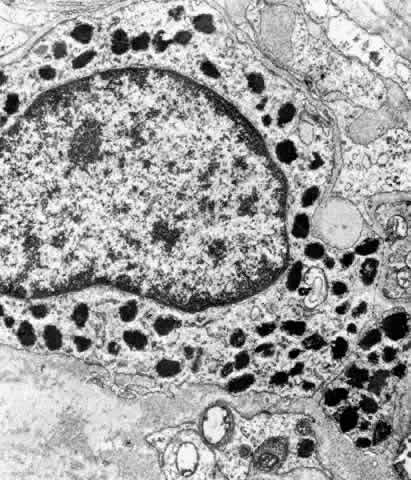

activity.28 In the moderately electron-lucent cytoplasm of the anterior NPE particularly, there

are large numbers of mitochondria near the base of the cell

and rough endoplasmic reticulum (RER) in single cisternae or parallel

stacks near the nucleus, where Golgi complexes are also common22 (Fig. 16). The mitochondria are of importance in providing energy for transport, and

the RER for processing of new protein. Clusters of free ribosomes

and occasional cilia are found in all areas. With aging, unusual whorled

formations of RER are described near the cell base in the pars plicata, along

Fig. 16. Ciliary epithelium in the anterior pars plicata of a 19-year-old. Posterior

chamber surface (PC) of the nonpigmented epithelium (NPE) has a sawtooth

pattern seen irregularly throughout this layer with aging. Mitochondria (m) are

large, plentiful, and show artifactual hydropic change. Rough

endoplasmic reticulum is present below the nuclei (asterisk). Note

that the apices of the pigmented epithelial cells (PE) are conical, with

prolongations of NPE between them. (X 8320) Fig. 16. Ciliary epithelium in the anterior pars plicata of a 19-year-old. Posterior

chamber surface (PC) of the nonpigmented epithelium (NPE) has a sawtooth

pattern seen irregularly throughout this layer with aging. Mitochondria (m) are

large, plentiful, and show artifactual hydropic change. Rough

endoplasmic reticulum is present below the nuclei (asterisk). Note

that the apices of the pigmented epithelial cells (PE) are conical, with

prolongations of NPE between them. (X 8320)